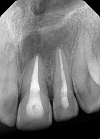

This case report highlights the successful healing of a large periapical lesion through non-surgical root canal retreatment. A 29-year-old male patient presented with a significant radiolucency associated with teeth #21 and #22, initially treated non-surgically. Despite the lesion's size, the treatment, which included thorough canal disinfection and obturation, led to substantial healing. A follow-up cone-beam computed tomography (CBCT) scan after one year confirmed the buccal cortical bone reformation and improvement in the incisive canal area except for the apical region of #21. Subsequently, root canal retreatment was performed for #21. Complete healing was achieved after two years, demonstrating that even extensive periapical lesions can be effectively treated with non-surgical endodontic retreatment, avoiding invasive surgical intervention.